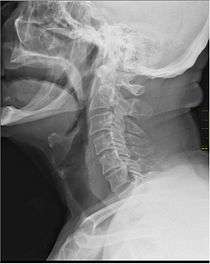

X-Ray showing the throat. Note the dark colored band anterior to the spine. | |